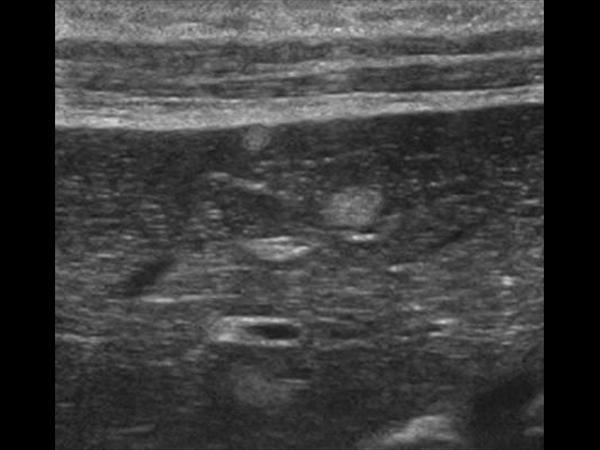

Gan nhiễm mỡ

» Thông tin: Nữ giới – 56 tuổi.

» Lâm sàng: Kiểm tra sức khỏe.